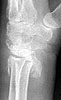

Seeking advice on management of 1 month old untreated distal radius fracture in non dominant hand of a 64 years old watchman. Pictures and xrays attached.

Valgus stress